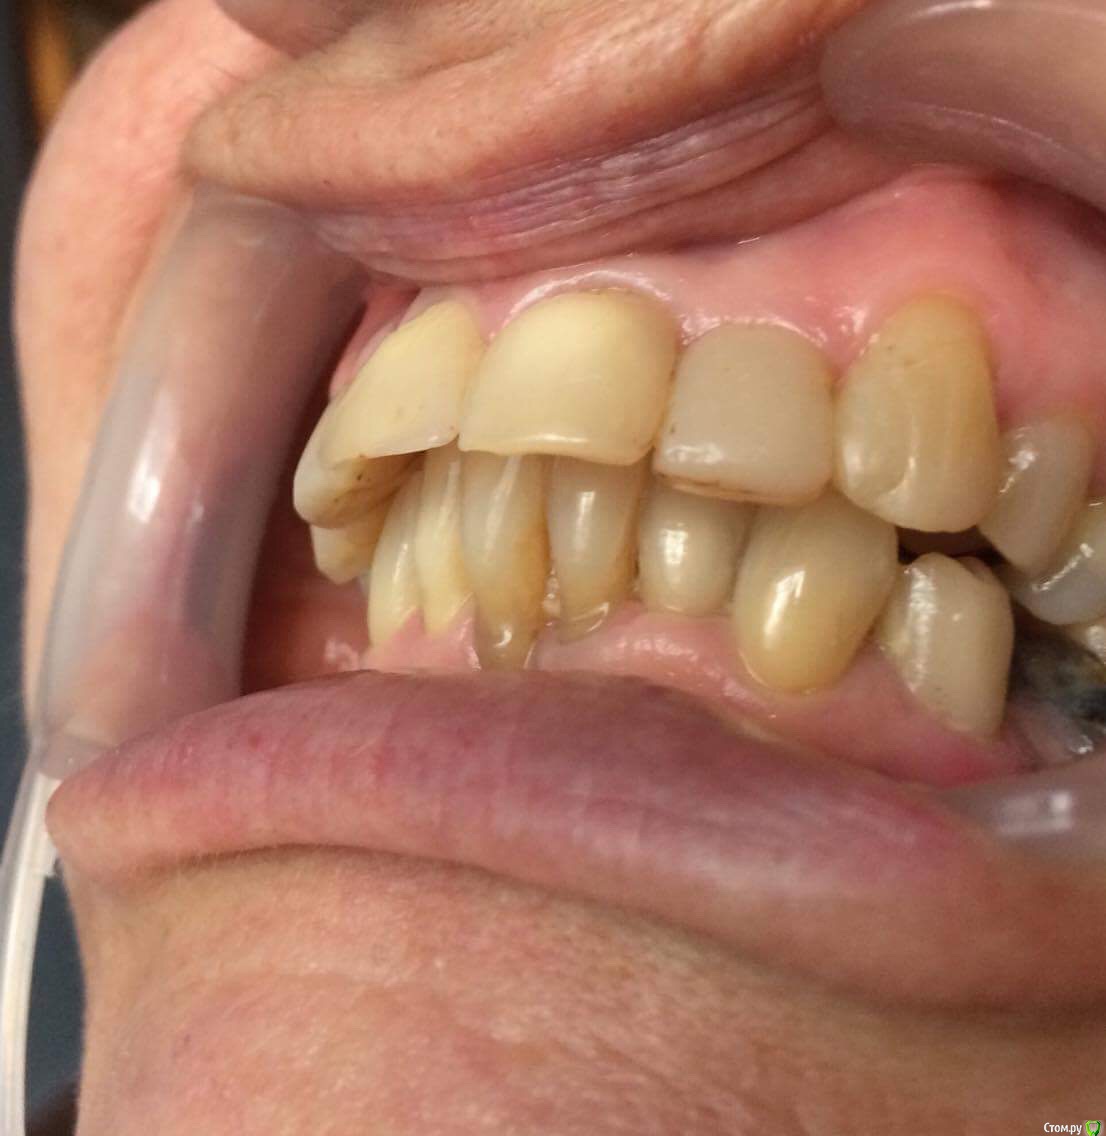

dr.Dre Опубликовано 27 июня, 2017 Поделиться Опубликовано 27 июня, 2017 Добрый день коллеги тему уже создавал но дал мало информации ,пациентка 58 лет .Помогите составить план лечения,имплантацию не потянет .Нужно ли здесь поднимать прикус? Ссылка на комментарий

chervoncevdaniil Опубликовано 27 июня, 2017 Поделиться Опубликовано 27 июня, 2017 (изменено) Док,фотопротокол вам мягко говоря подтянуть надо, боковые вообще не видно.Про имплантацию мы поняли,а остальное?Устраивает ли ее эстетика фронта,или просто хочет чтобы было чем жевать в боковом отделе?Как к съемному протезированию относится,потому что иначе вы 3 сегмент не закроете.Плюс вы же понимаете,что если вы прикус поднимете,то автоматически под коронки/виниры/накладки пойдут все зубы,включая интактный нижний фронт и витальные верх это вы с пациенткой обсудили? Может после этого уже и на имплантацию мотивация появится? Изменено 27 июня, 2017 пользователем chervoncevdaniil Ссылка на комментарий

dr.Dre Опубликовано 27 июня, 2017 Автор Поделиться Опубликовано 27 июня, 2017 Док,фотопротокол вам мягко говоря подтянуть надо, боковые вообще не видно.Про имплантацию мы поняли,а остальное?Устраивает ли ее эстетика фронта,или просто хочет чтобы было чем жевать в боковом отделе?Как к съемному протезированию относится,потому что иначе вы 3 сегмент не закроете.Плюс вы же понимаете,что если вы прикус поднимете,то автоматически под коронки/виниры/накладки пойдут все зубы,включая интактный нижний фронт и витальные верх это вы с пациенткой обсудили? Может после этого уже и на имплантацию мотивация появится?Эстетика не устраивает,пациент хочет все делать полностью ,к сьемному относиться отрицательно.Хочет ровные красивые зубы Ссылка на комментарий

chervoncevdaniil Опубликовано 27 июня, 2017 Поделиться Опубликовано 27 июня, 2017 (изменено) Ну в таком случае я не знаю как вы будете низ боковые сегменты протезировать,но 36 однозначно под удаление,26 и 27 в связи с деформацией плоскости видимо тоже придется,47 и 17 под вопросом и у нее получаются концевые дефекты.Опять же повторюсь,очень плохо видно что в боковом отделе,но настолько прикус вы навряд ли поднимете,чтобы и боковые зубы остались и при этом фронт не получился как у лошади,потому что по размерам резцы и клыки абсолютно нормальные Изменено 27 июня, 2017 пользователем chervoncevdaniil Ссылка на комментарий